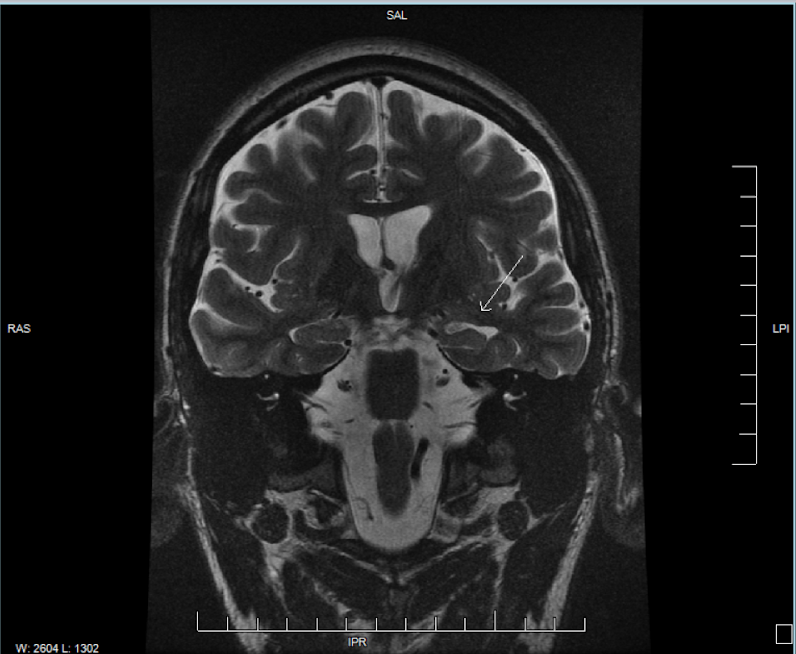

A closer look at my brain

I suffered a severe traumatic brain injury and was diagnosed with posttraumatic epilepsy early on in my recovery. Recently, however, I decided to see an epileptologist, or a neurologist who specializes in treating patients with epilepsy. Finding it weird that it never came to my mind to see an epileptologist, I decided to do so back in August of 2022 because I was having more frequent seizures. The doctor decided to order MRI scans of my brain; the MRI images showed left-sided MTS, and furthermore MTLE. One of the MRI images that shows the evidence of MTS is shown below.

The white tissue that the arrow is pointing to is scar tissue, indicative of left-sided MTS